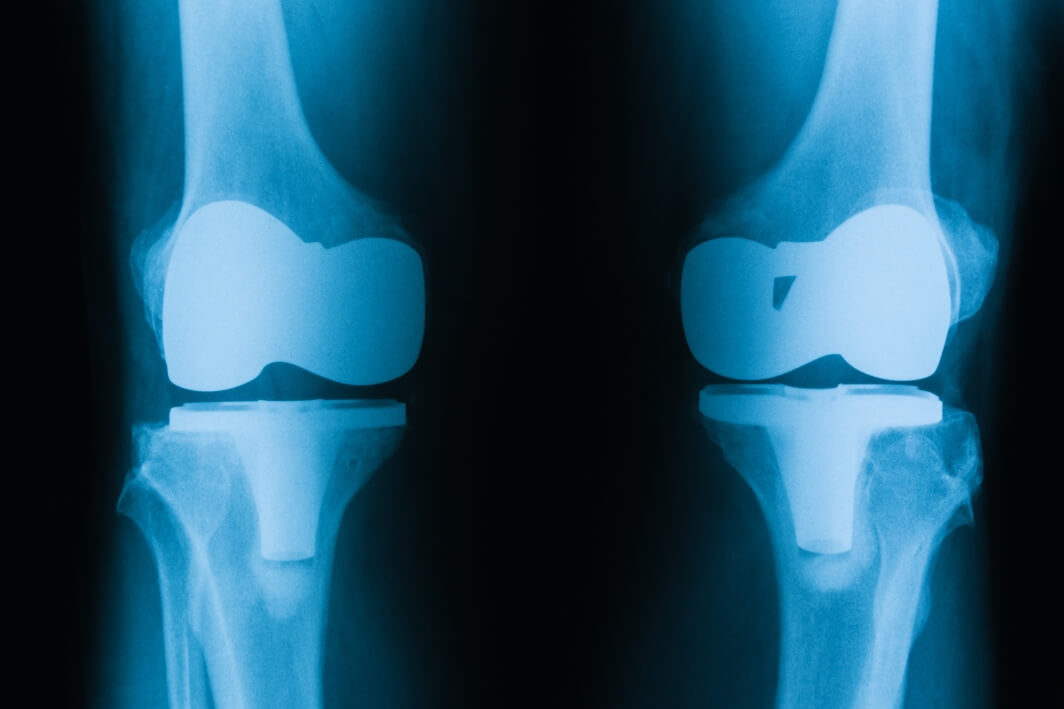

Dr. Amit Meena is a specialized center dedicated to treating complex knee problems, offering top-quality, research-backed joint replacement and sports medicine treatments. Because we focus exclusively on these specific medical areas, we have developed exceptional expertise and built a strong reputation for excellence both in India and around the world. Dr. Amit Meena is a specialized center dedicated to treating complex knee problems, offering top-quality, research-backed joint replacement and sports medicine treatments. Because we focus exclusively on these specific medical areas, we have developed exceptional expertise and built a strong reputation for excellence both in India and around the world.